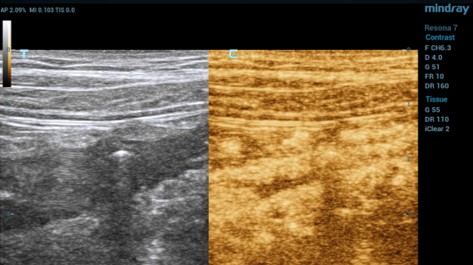

Дополнительные возможности ультразвукового исследования при воспалительных заболеваниях кишечника – эластография кишечной стенки, применение эхоконтрастных препаратов